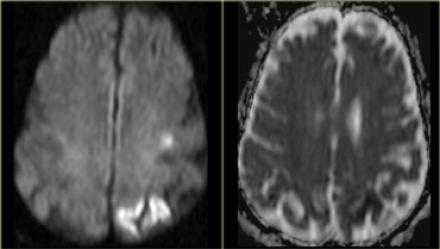

Диффузно-взвешенное изображение.

DWI наиболее чувствительна к инсульту. В результате цитотоксического отека возникает дисбаланс внеклеточной воды к Броуновскому движению, поэтому данные изменения выявляются отлично на DWI. В норме протоны воды диффундируют внеклеточно, поэтому теряется сигнал. Высокая интенсивность сигнала на DWI указывает на ограничение протонов воды диффундировать внеклеточно.

Представлены ДВИ инфаркт передней, задней, средней мозговой артерии.

Обратите внимание на изображение и предположите, где патология. После продолжите чтение. Вывод:

Есть некоторая гиподенсность и отек в левой лобной доли со старостью борозд в сравнении с контр-латеральной стороной. Далее DWI снимки того же пациента. После просмотра DWI нет сомнения, что это инфаркт. Именно поэтому DWI называют инсульт последовательностью.